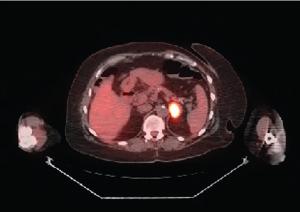

Breast metastasis from extramammary malignancy is rare, with a reported incidence rate of 0.4% to 1.3% in the published literature. The primary malignancies that most commonly metastasize to the breast are leukemia, lymphoma, and malignant melanoma. Here, we report a very rare case of metastatic EGFR-mutated non–small cell lung cancer (NSCLC) in the breast detected by screening mammography. The patient had initially been diagnosed with a clinical stage IIIA NSCLC and had been treated with neoadjuvant chemoradiation followed by curative-intent surgery. Several interesting aspects of the case, along with a discussion of evolving adjuvant and frontline metastatic management options in EGFR-mutated NSCLC, will be presented.